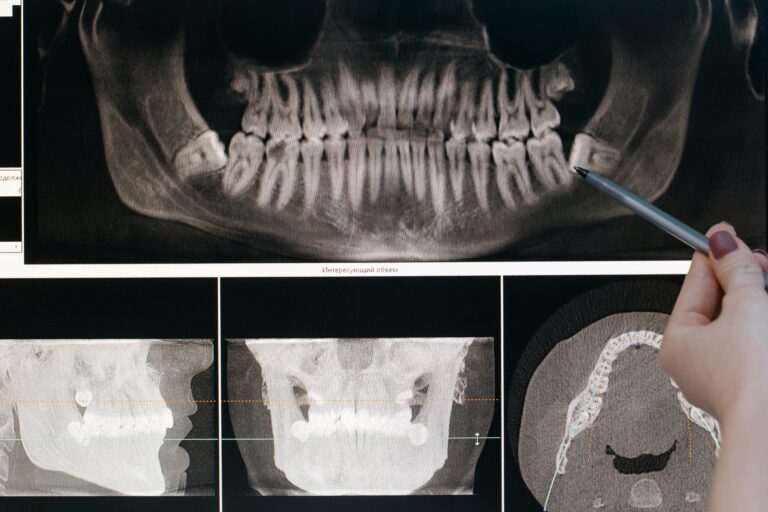

Dental implantation is an advanced branch of surgical dentistry focused on restoring missing teeth by placing artificial roots (implants) into the jawbone. This method...